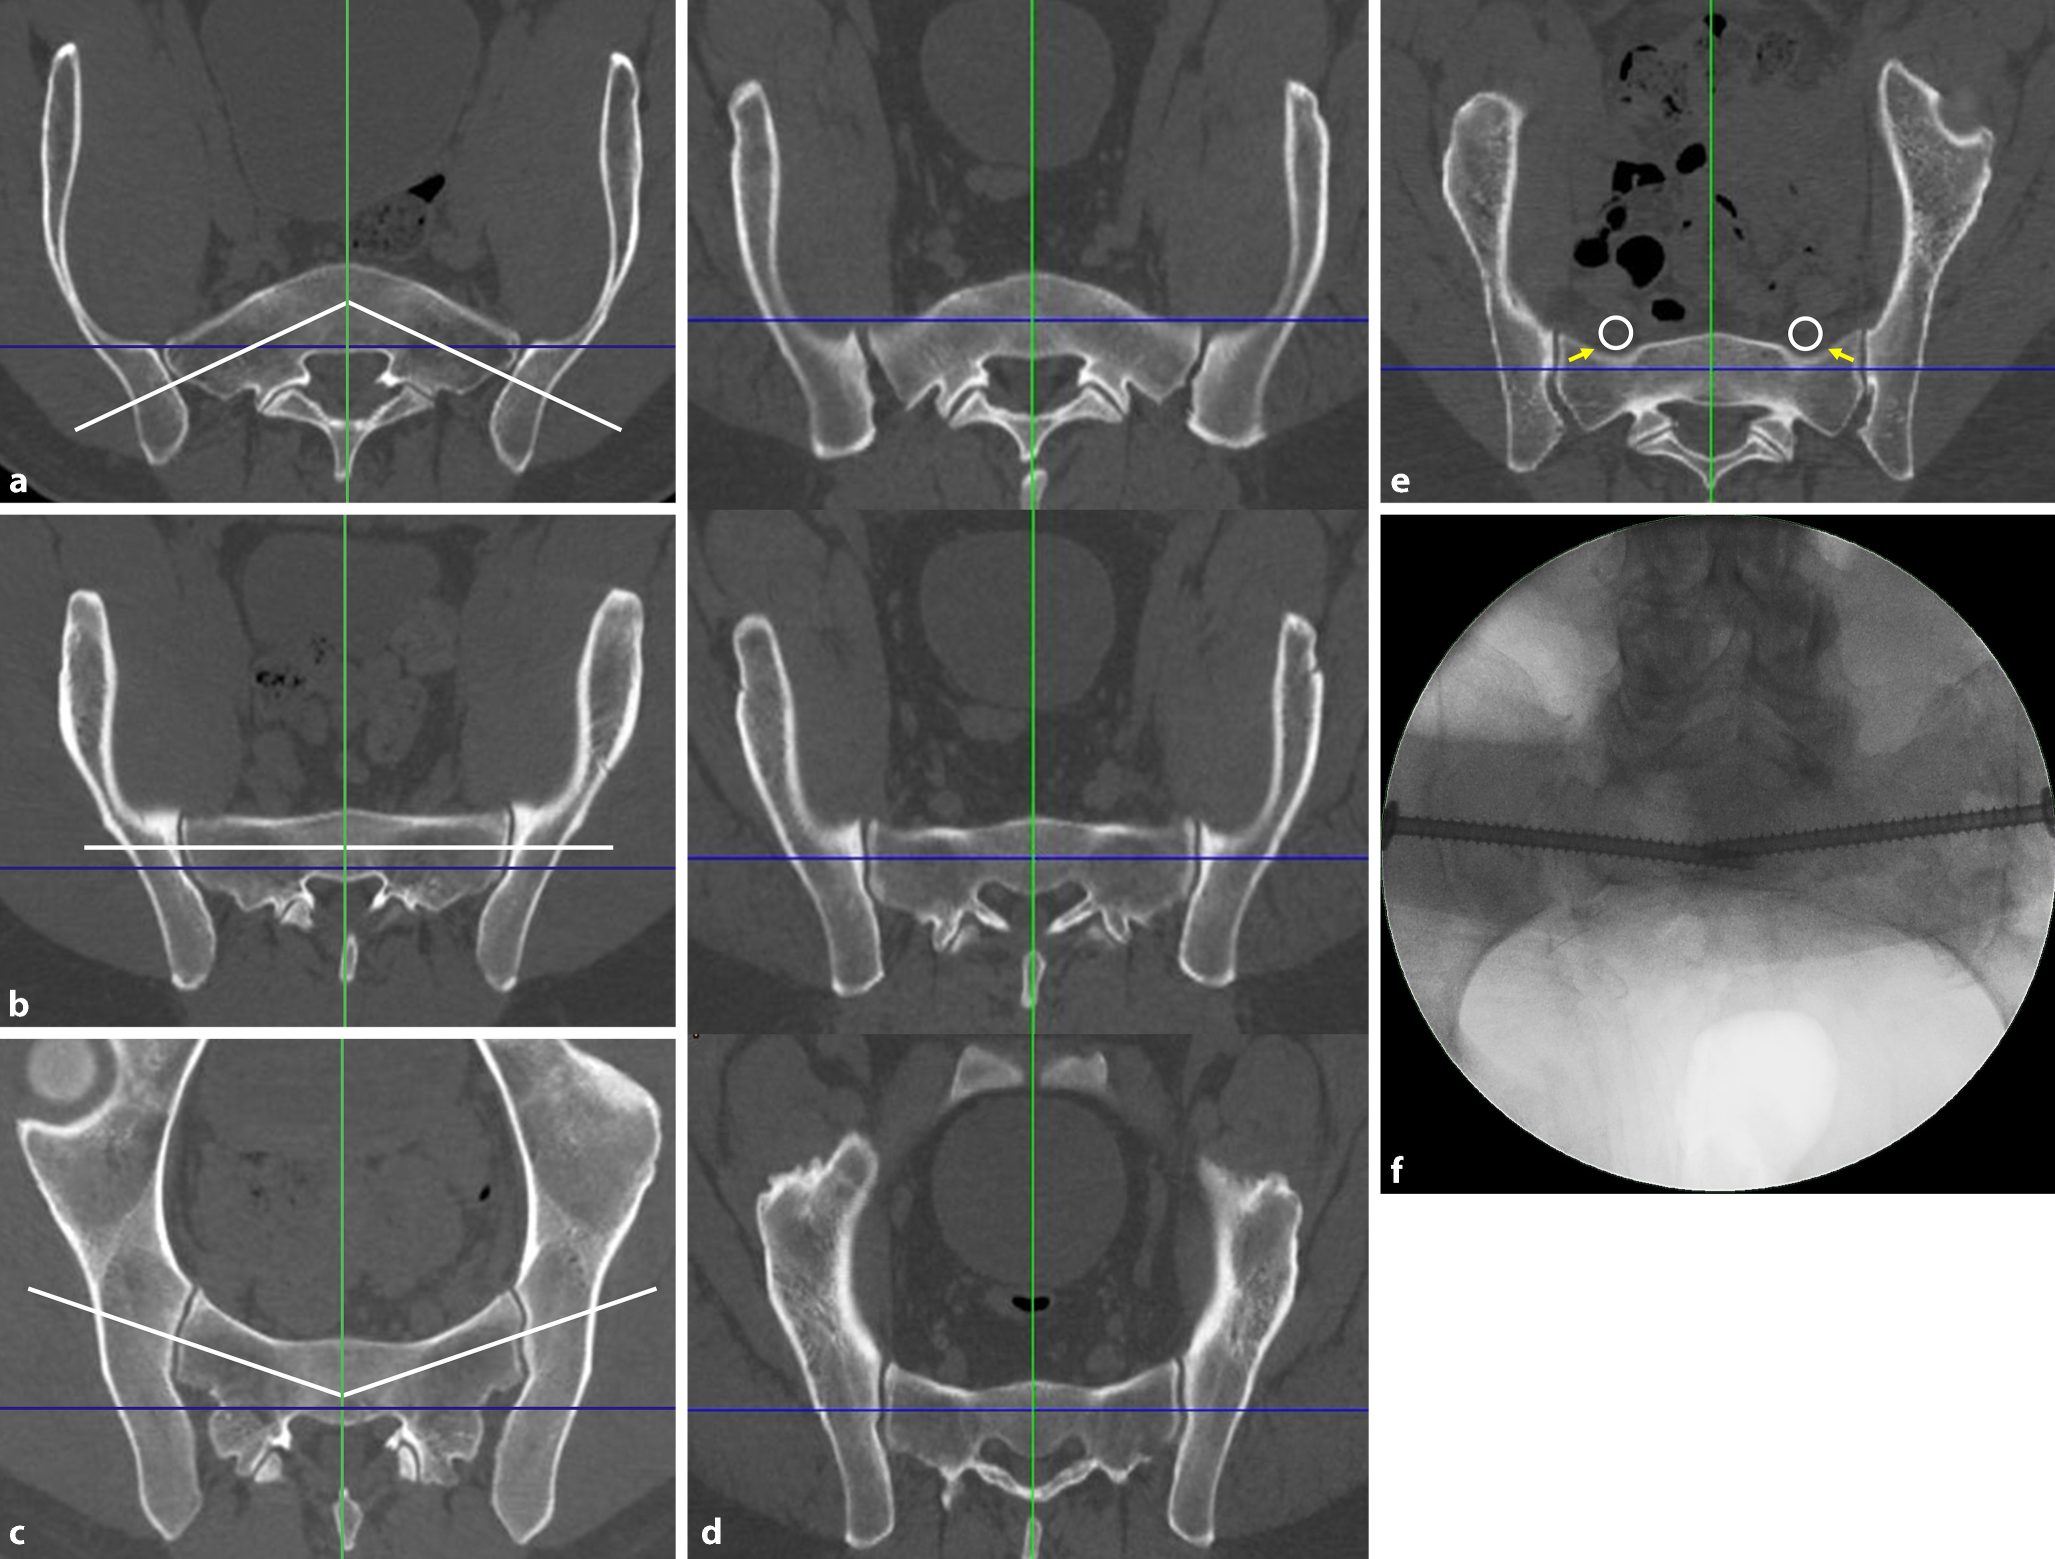

Second step—defining the corridor type and assessing the “notch”

The definition of the corridor type and the assessment of the “notch” is a prerequisite for the determination of the screw trajectory. The corridor type is defined in the inlet view based on the axis of the osseous corridor (white line) in comparison to the coronal axis (blue line).

Second step of preoperative work-up: defining the corridor type and assessing the “notch”. a Ascending type, b horizontal type, c descending type, d corridor types at different levels of S1 in the same patient, e “notch”, f intraoperative image. Blue line coronal axis, green line sagittal axis, white line osseous corridor, white circle nerve roots L5, yellow arrows notch

Ascending type (Fig. 2a): The axis of the osseous corridor runs from lateral posterior to medial anterior. The anterior surface of the sacrum has a convex shape.

Horizontal type (Fig. 2b): The axis of the osseous corridor runs parallel to the coronal axis. The anterior surface of the sacrum has a flat shape.

Descending type (Fig. 2c): The axis of the osseous corridor runs from lateral anterior to medial posterior. The anterior surface of the sacrum has a concave shape.

The corridor type may change within a single sacral body along the craniocaudal extension of the sacrum. Accordingly, the corridor type is assessed in the upper and the lower third of the sacral body as well. Figure 2d shows a sacrum with an ascending corridor in the upper third, a horizontal corridor in the middle third and a descending corridor in the lower third.

A “notch” (yellow arrow in Fig. 2e) is defined as an indentation of the anterior cortex of the sacral ala between the SI joint and the sagittal midline [7]. A notch results in a reduced anteroposterior diameter of the osseous corridor in this part of the screw trajectory. This increases the risk of screw misplacement, which may lead to iatrogenic nerve lesions due to the close vicinity of the notch and the nerve roots L5 (white circle). An indentation of the anterior cortex of the sacral ala requires a posterior entry point and an oblique screw trajectory.

The notch may not be visible in the two-dimensional intraoperative inlet view due to overlapping of the anterior cortex of S1 and S2. This intraoperative image (Fig. 2f) shows the same patient as in Fig. 2e.